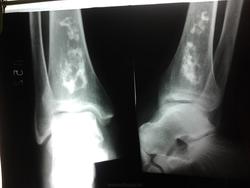

Пациент(мужчина) 50 лет.Подвернул ногу.Обратился с жалобами на боли в голеностопном суставе.При осмотре боль,припухлость в области лодыжек,гиперемии нет.Движения в полном обьёме.На снимке случайная находка.Ваше мнение коллеги?